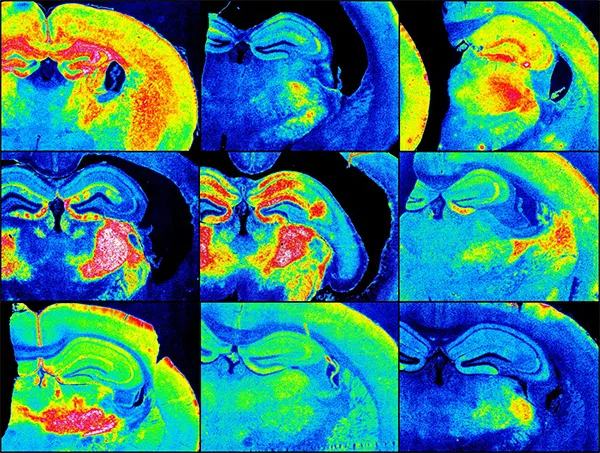

Images of the brain

Different types of prion disease provoke different responses in the brain.

When the brain is infected by prions, the astrocytes become activated and express the CD44 antigen. Each type of prion prompted a unique pattern of this reaction in the astrocytes in specific areas of the brain, the scientists observed.